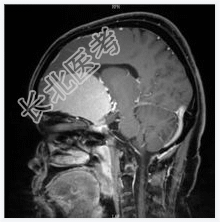

- [材料题] 患者女,55岁,视力下降数月。查体:视力下降,余神经体征阴性。

- 简答题1、诊断及依据是什么?

- 简答题2、鉴别诊断有什么?